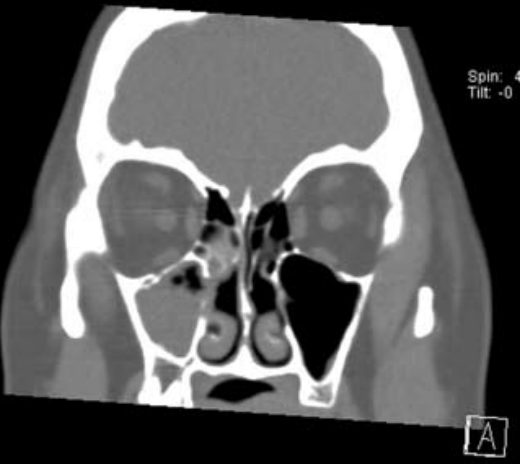

Rhino Sinusitis | ENT Kent from entkent.com Nasal polyps can grow anywhere on the lining of the nose or the sinuses. Small nasal polyps usually cause few problems, but larger ones can affect breathing and reduce sense of smell. Find out what happens when you have an operation to remove nasal polyps. They are powerful to shrink down the tumor and prevent the nose from further infection. Nasal polyps are not cancer. Coronal section showing soft tissue windows rather than bony windows. There are two types of nasal polyps, antrochoanal polyps and ethmoidal polyps. Nasal polyps are soft growths that line the inside of your nose or sinuses.